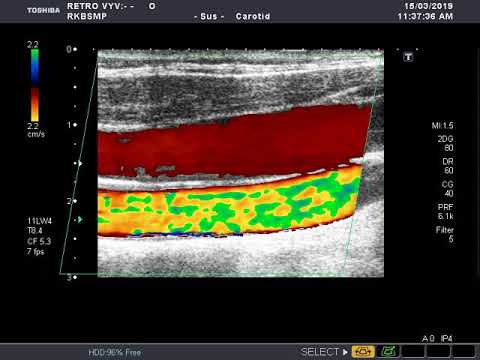

Яремная вена на узи

Яремная вена на узи 111 фотографий